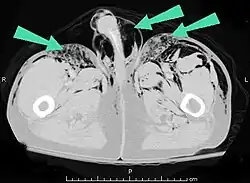

| An abdominal CT scan of a patient with subcutaneous emphysema (arrows) | |